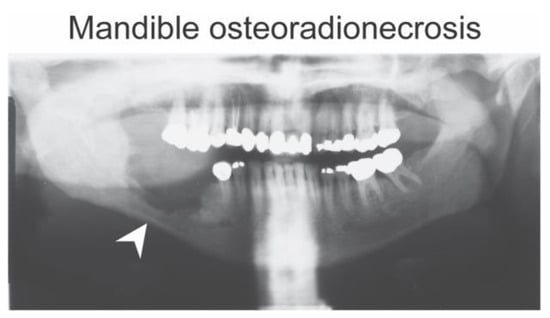

- Miyamoto, I.; Tanaka, R.; Kogi, S.; Yamaya, G.; Kawai, T.; Ohashi, Y.; Takahashi, N.; Izumisawa, M.; Yamada, H. Clinical Diagnostic Imaging Study of Osteoradionecrosis of the Jaw: A Retrospective Study. J. Clin. Med. 2021, 10, 4704. [Google Scholar] [CrossRef] [PubMed]